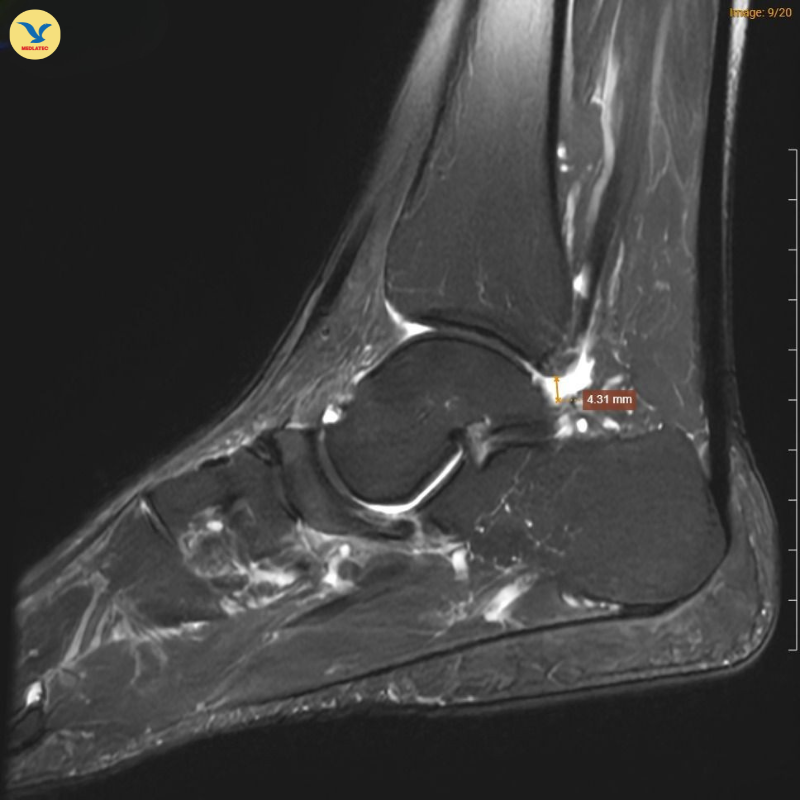

| MRI chân trái ghi nhận hình ảnh thoái hóa khớp và phù nề |

Đồng thời ghi nhận hình ảnh tổn thương gai xương thoái hóa khớp cổ chân trái, ổ phù tủy xương vị trí xương sên, phù nề dây chằng chày mác sau, dây chằng sên mác sau, dây chằng gót chày và dây chằng tam giác cổ chân, dịch khớp cổ chân, phù nề phần mềm quanh khớp cổ chân.